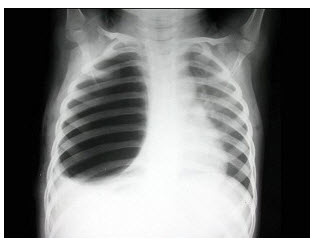

84、单项选择题

女,45岁,寒战、高热1周,WBC:1.8×109/L,胸片如图,应首先考虑()

A.肺结核

B.肺癌

C.肺脓肿

D.肺隔离症

E.大叶性肺炎

点击查看答案